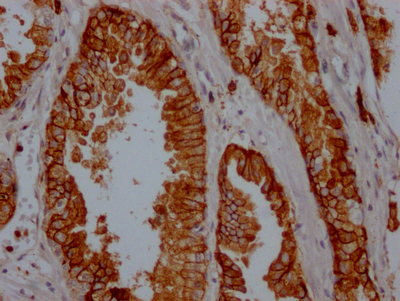

ELISA, WB, IHC

| CD38 | CD38 Recombinant Monoclonal Antibody | Human | ELISA, WB, IHC | CSB-RA796695A0HU |